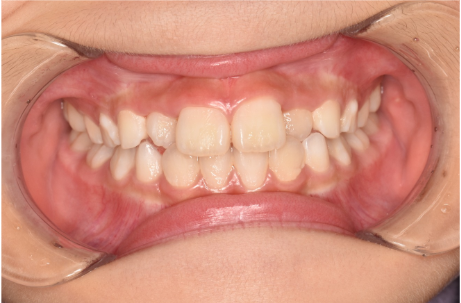

治療前

| ご相談内容 | 「上の前歯が奥に入ったり、手前に出てきたりしてガタガタ。かみ合わせも上下反対になっている」と保護者様が、お子様のお口の状況を気にされてご来院をいただきました。 |

| カウンセリング・診断結果 | お口の中を確認したところ、左側の前歯の一部(側切歯/B)のかみ合わせが上下反対になっていました。 矯正治療のための精密検査を行った結果、骨格に大きな問題はありませんでした。そのためご相談にあった前歯のガタガタに関してはスムーズに矯正を進めることができると判断しました。 ただ、犬歯(C)が生えている状況(萌出状況)を見ると今後、永久歯が生えた段階で「永久歯列の矯正(2期治療)」を行う必要性が生まれるかもしれないと考えました。 |